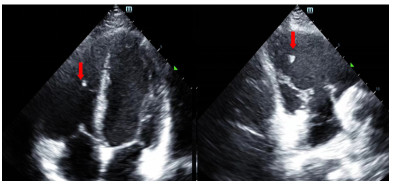

患者入院后无胸闷气促等不适主诉。入科查体:体温36.5 ℃,脉搏86次/min,呼吸频率16次/min,血压106/54 mmHg(1 mmHg=0.133 kPa),指尖氧饱和度99%~100%(未吸氧情况下),神清,瞳孔等大等圆,对光反射可,双肺呼吸音清,无明显干湿啰音,听诊心脏,律齐,无病理性杂音,左侧前臂近端及远端各一创面包扎,敷料干燥,未见明显渗出,左上肢肌力无法配合(考虑臂丛阻滞麻醉未完全恢复),余四肢肌力肌张力感觉无明显异常。立即完善相关检查(图 3、4),通过X线以及CT定位异物,超声评估异物在心脏中的活动情况及与心脏搏动时与瓣膜以及周围组织结构关系,可见异物在心脏内较固定,未影响瓣膜运动。同时血化验(动脉血气、感染指标、心肌酶谱、肌钙蛋白、D二聚体等)及心电图未见明显异常,请心胸外科会诊后建议暂予以抗炎保守对症处理。

| 图 4 外伤后第三次评估异物情况心脏超声检查图像 |